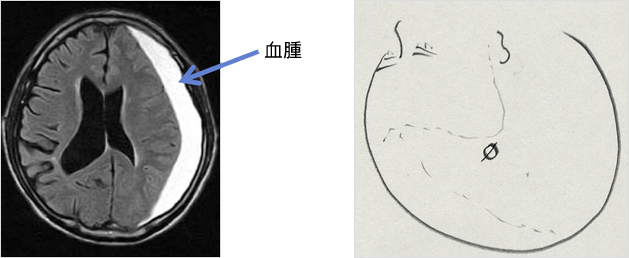

解答 解説 けいれん 意識障害で搬送された5カ月女児 実践 画像診断q A 羊土社 レジデントノート 羊土社

慢性硬膜下血腫

乳幼児の急性硬膜下血腫 虐待疑いは3割 国手引の見直し必要性指摘 6病院共同研究 毎日新聞

外傷性硬膜下血腫の後遺症 症状は手術で治る 予後不良の後遺障害慰謝料はいくら アトム法律事務所弁護士法人